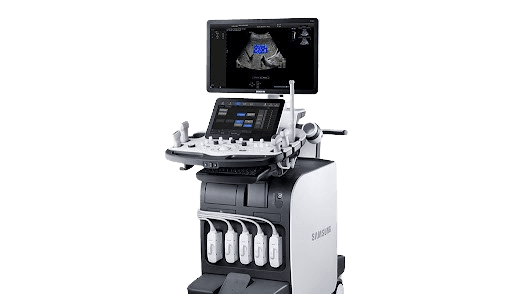

Ultrasound Exam Basic ultrasound exam checking pelvic reproductive organ structure. Real-time visualization of uterine fibroids, ovarian cysts, and endometrial thickness for early detection.